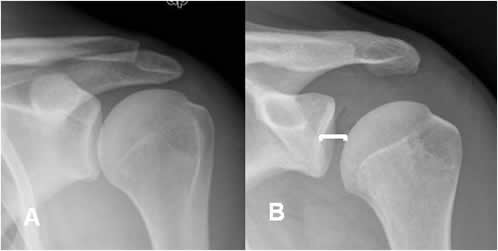

Espacio articular glenohumeral:

Es la distancia entre el borde medial del húmero y la parte anterior de la glenoides.

Su valor normal es menor de 6 mm y se aumenta en casos de luxación posterior. (1, 10).

(Fig 44).

Fig 44. Luxación posterior.

A: Rx AP. Espacio glenohumeral normal.

B: Rx AP. Aumento del espacio glenohumeral, por luxación posterior.